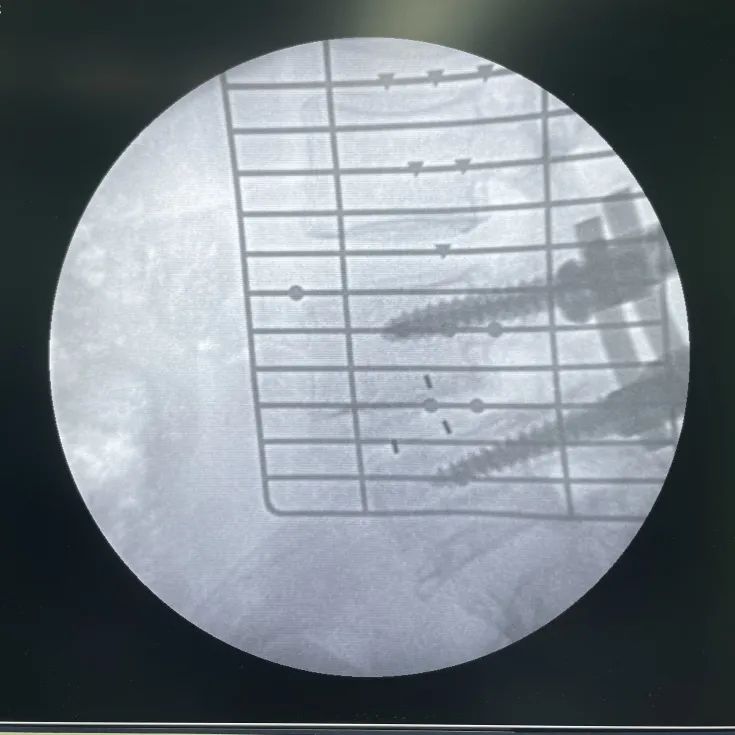

術(shù)中影像

患者右側(cè)臥位,透視確認(rèn)皮膚切口區(qū)域

切皮暴露,透視確認(rèn)手術(shù)節(jié)段